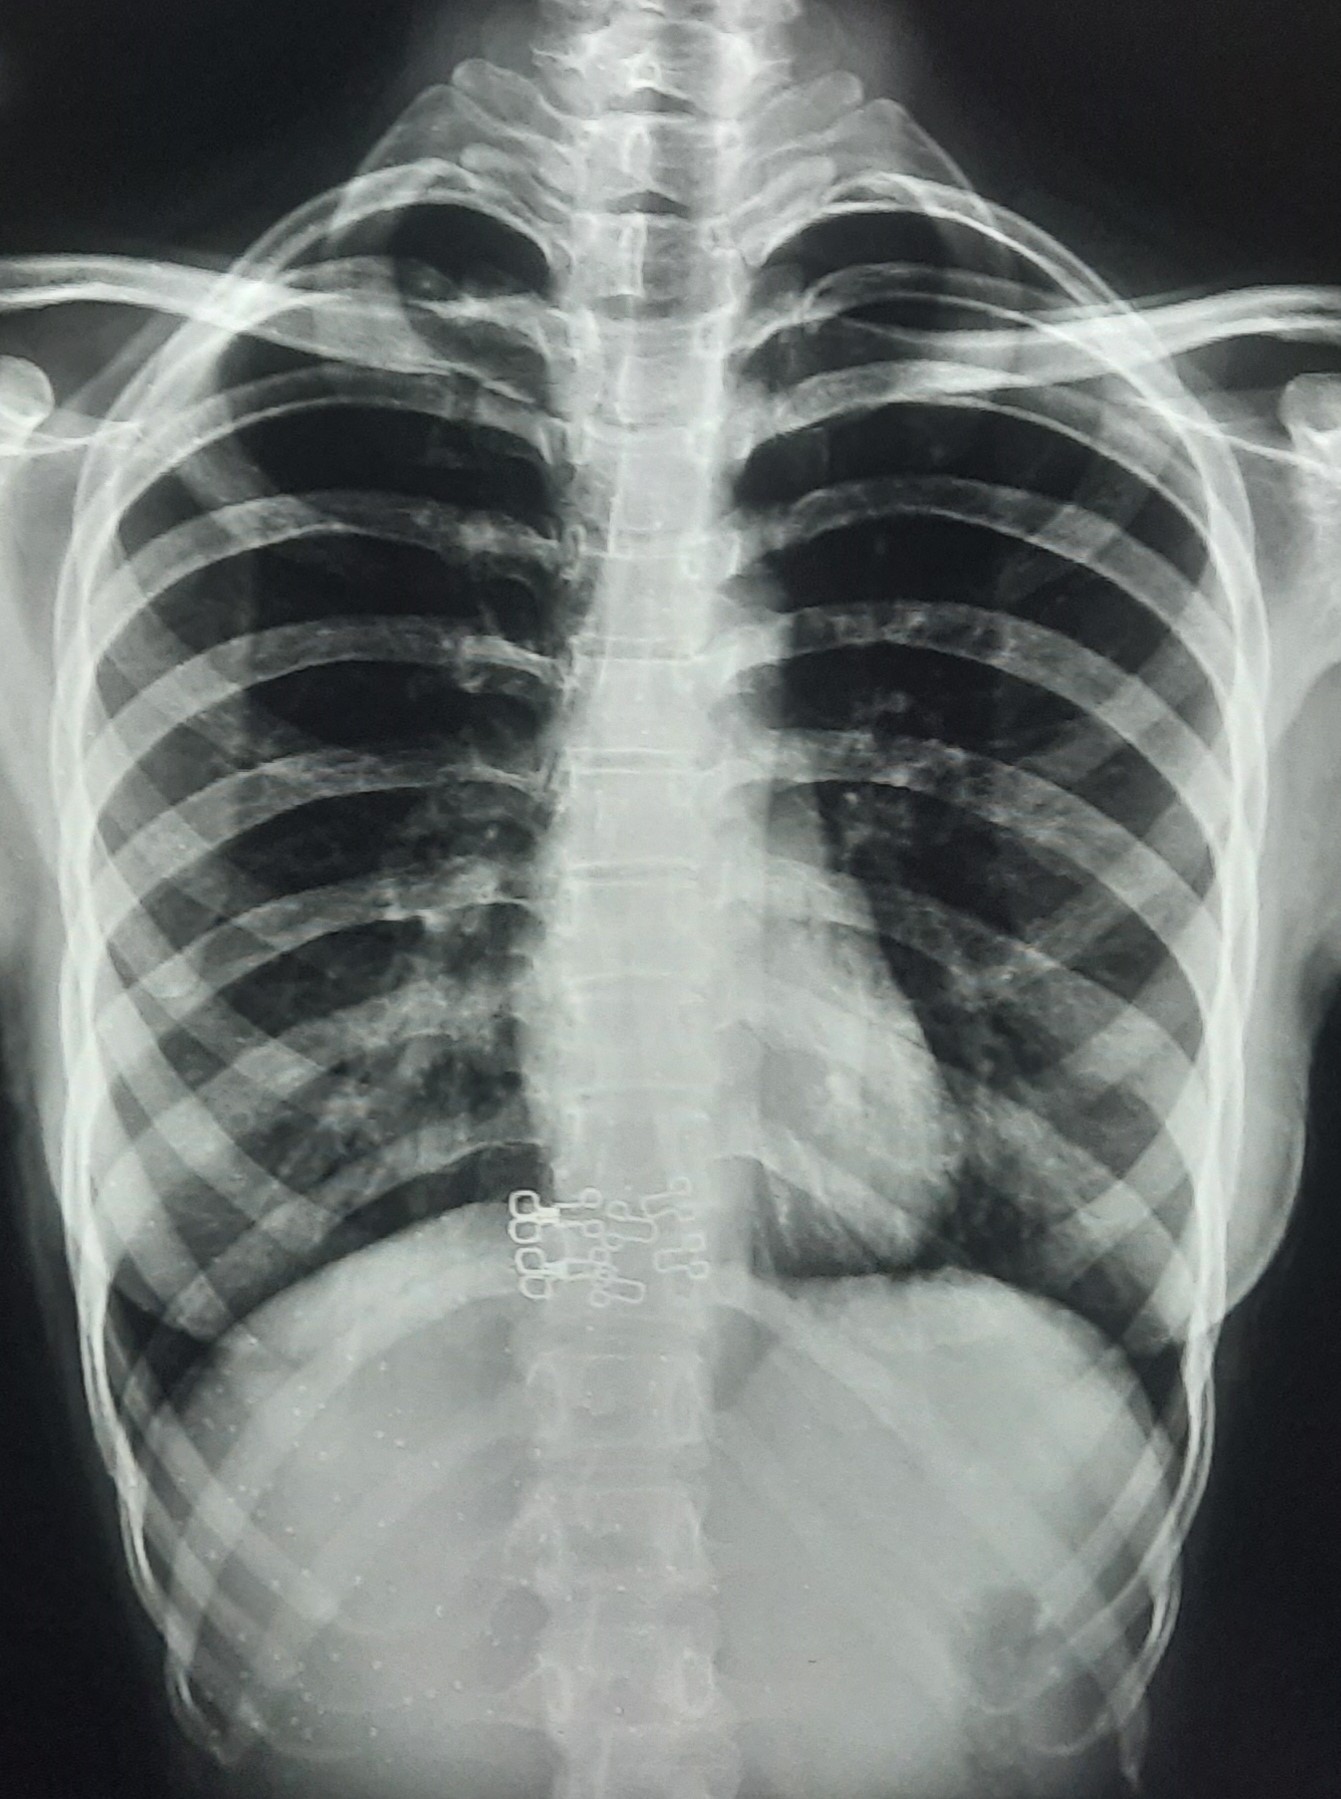

| 296 | IGGMC, Nagpur, Nagpur | P2 | 29-4176 | Mahamad Faiyaz Ansari | Consent taken on Paper | 45 Yrs. |

Provisional Diag : Lung Fibrosis/PTB

Final Diag : ? |

TB Case (Confirmed) | Abnormality visible on x-ray |